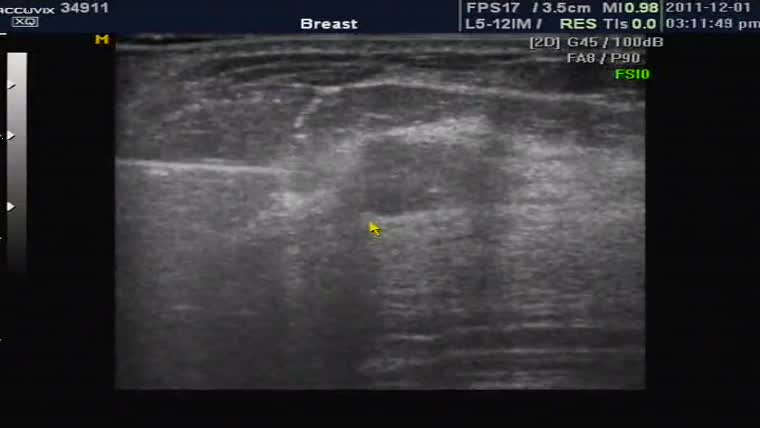

유방 결절의 조직 검사인 총조직 검사 동영상입니다.

좌측에 하얗게 길쭉하게 보이는 것이 총조직 검사 바늘의 모습이고 중심부의 검은 타원형 부분이 결절입니다.

절개를 하지 않고 바늘을 찔러 조직 일부를 채취하는 검사가 총조직 검사입니다.